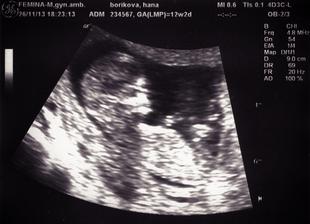

Termín pôrodu máme 8.jún 2014, už aby to bolo 🙂)

1.9.2013 - posledná MS